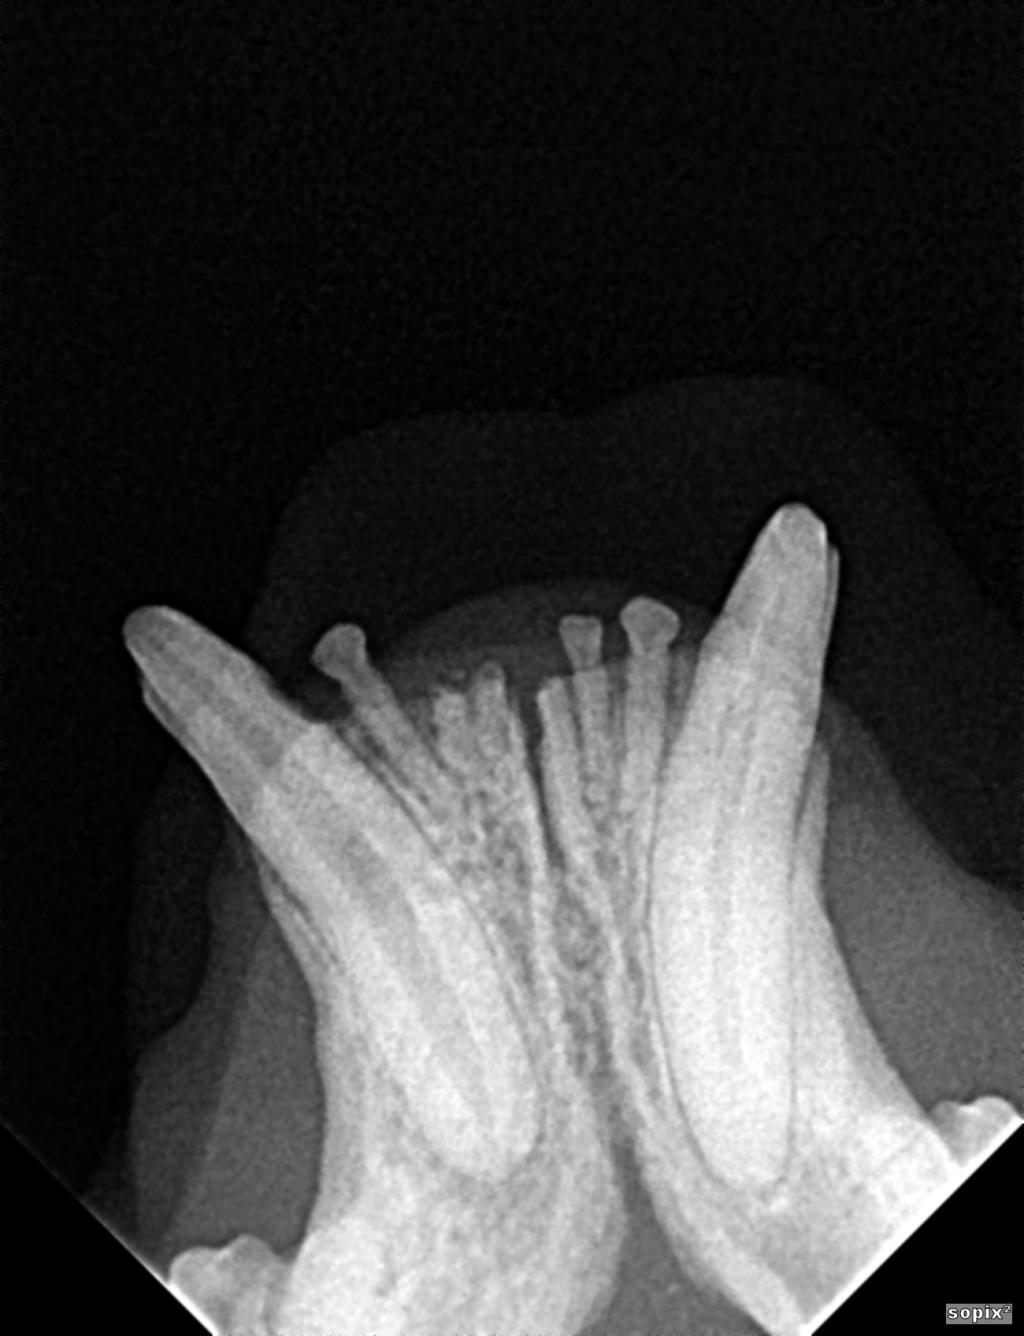

Bannière visuelle de présentation de la formation